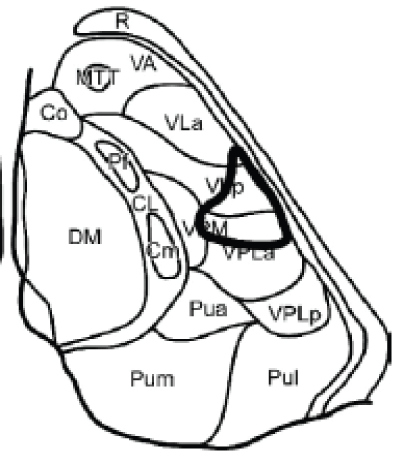

Tuberothalamic artery originates from the posterior communicating artery, irrigates the reticular nucleus, ventral anterior nucleus (VA), rostral part of the ventrolateral nucleus (VL), ventral pole of the medial dorsal nucleus (MD), ventral part of the internal medullary lamina, and anterior thalamic nuclei [anteromedial (AM), anteroventral (AV), and anterodorsal (AD)]. The anterior nuclei receive projections from the mammillothalamic tract (MTT) and are connected to the anterior limbic system (including the cingulated gyrus, hippocampus, parahippocampal formation, and orbitofrontal cortex) and to the medial and prefrontal cortex. Thereof injury in this area may lead to a particular behavioral pattern, including superimposition of unrelated information ("palipsychism" from the Greek "palin" (again) and "psyche" (soul), with parallel expression of mental activities, irrespective of sequential order) and perseverations ("anterior behavioral syndrome"), apathy, and amnesia [5] (Figure 4).

Paramedian arteries (arising from the P1 section of the posterior cerebral artery) supplies dorsomedian nucleus (divided into anteromedial magnocellular and posterolateral parvocellular mediodorsal nucleus) that receives projections from the amygdala and has connections to the prefrontal cortex and ventral pallidum; and the intralaminar nuclei: central lateral (CL), centromedian (CM), and parafascicular (Pf); the intralaminar nuclei are divided into the caudal part and the rostral part they project to the orbitofrontal and mediofrontal cortex, the motor and premotor cortex, and the internal globus pallidus. When the tuberothalamic artery is absent, the paramedian artery may assume that territory as well (Figure 5).

The inferolateral arteries arise from the P2 branch of the posterior cerebral artery, supply the major part of the ventral posterior nuclei (lateral [VPL], medial [VPM], and inferior [VPI]), as well as the ventral and lateral parts of the VL nucleus more rostrally. The ventrolateral nucleus has connections to the cerebellum and the motor and prefrontal cortex, while the ventroposterolateral nucleus receives inputs from the medial lemniscal and spinothalamic pathways, finally the ventroposteromedial nucleus receives inputs from the trigeminothalamic pathway (Figure 6).